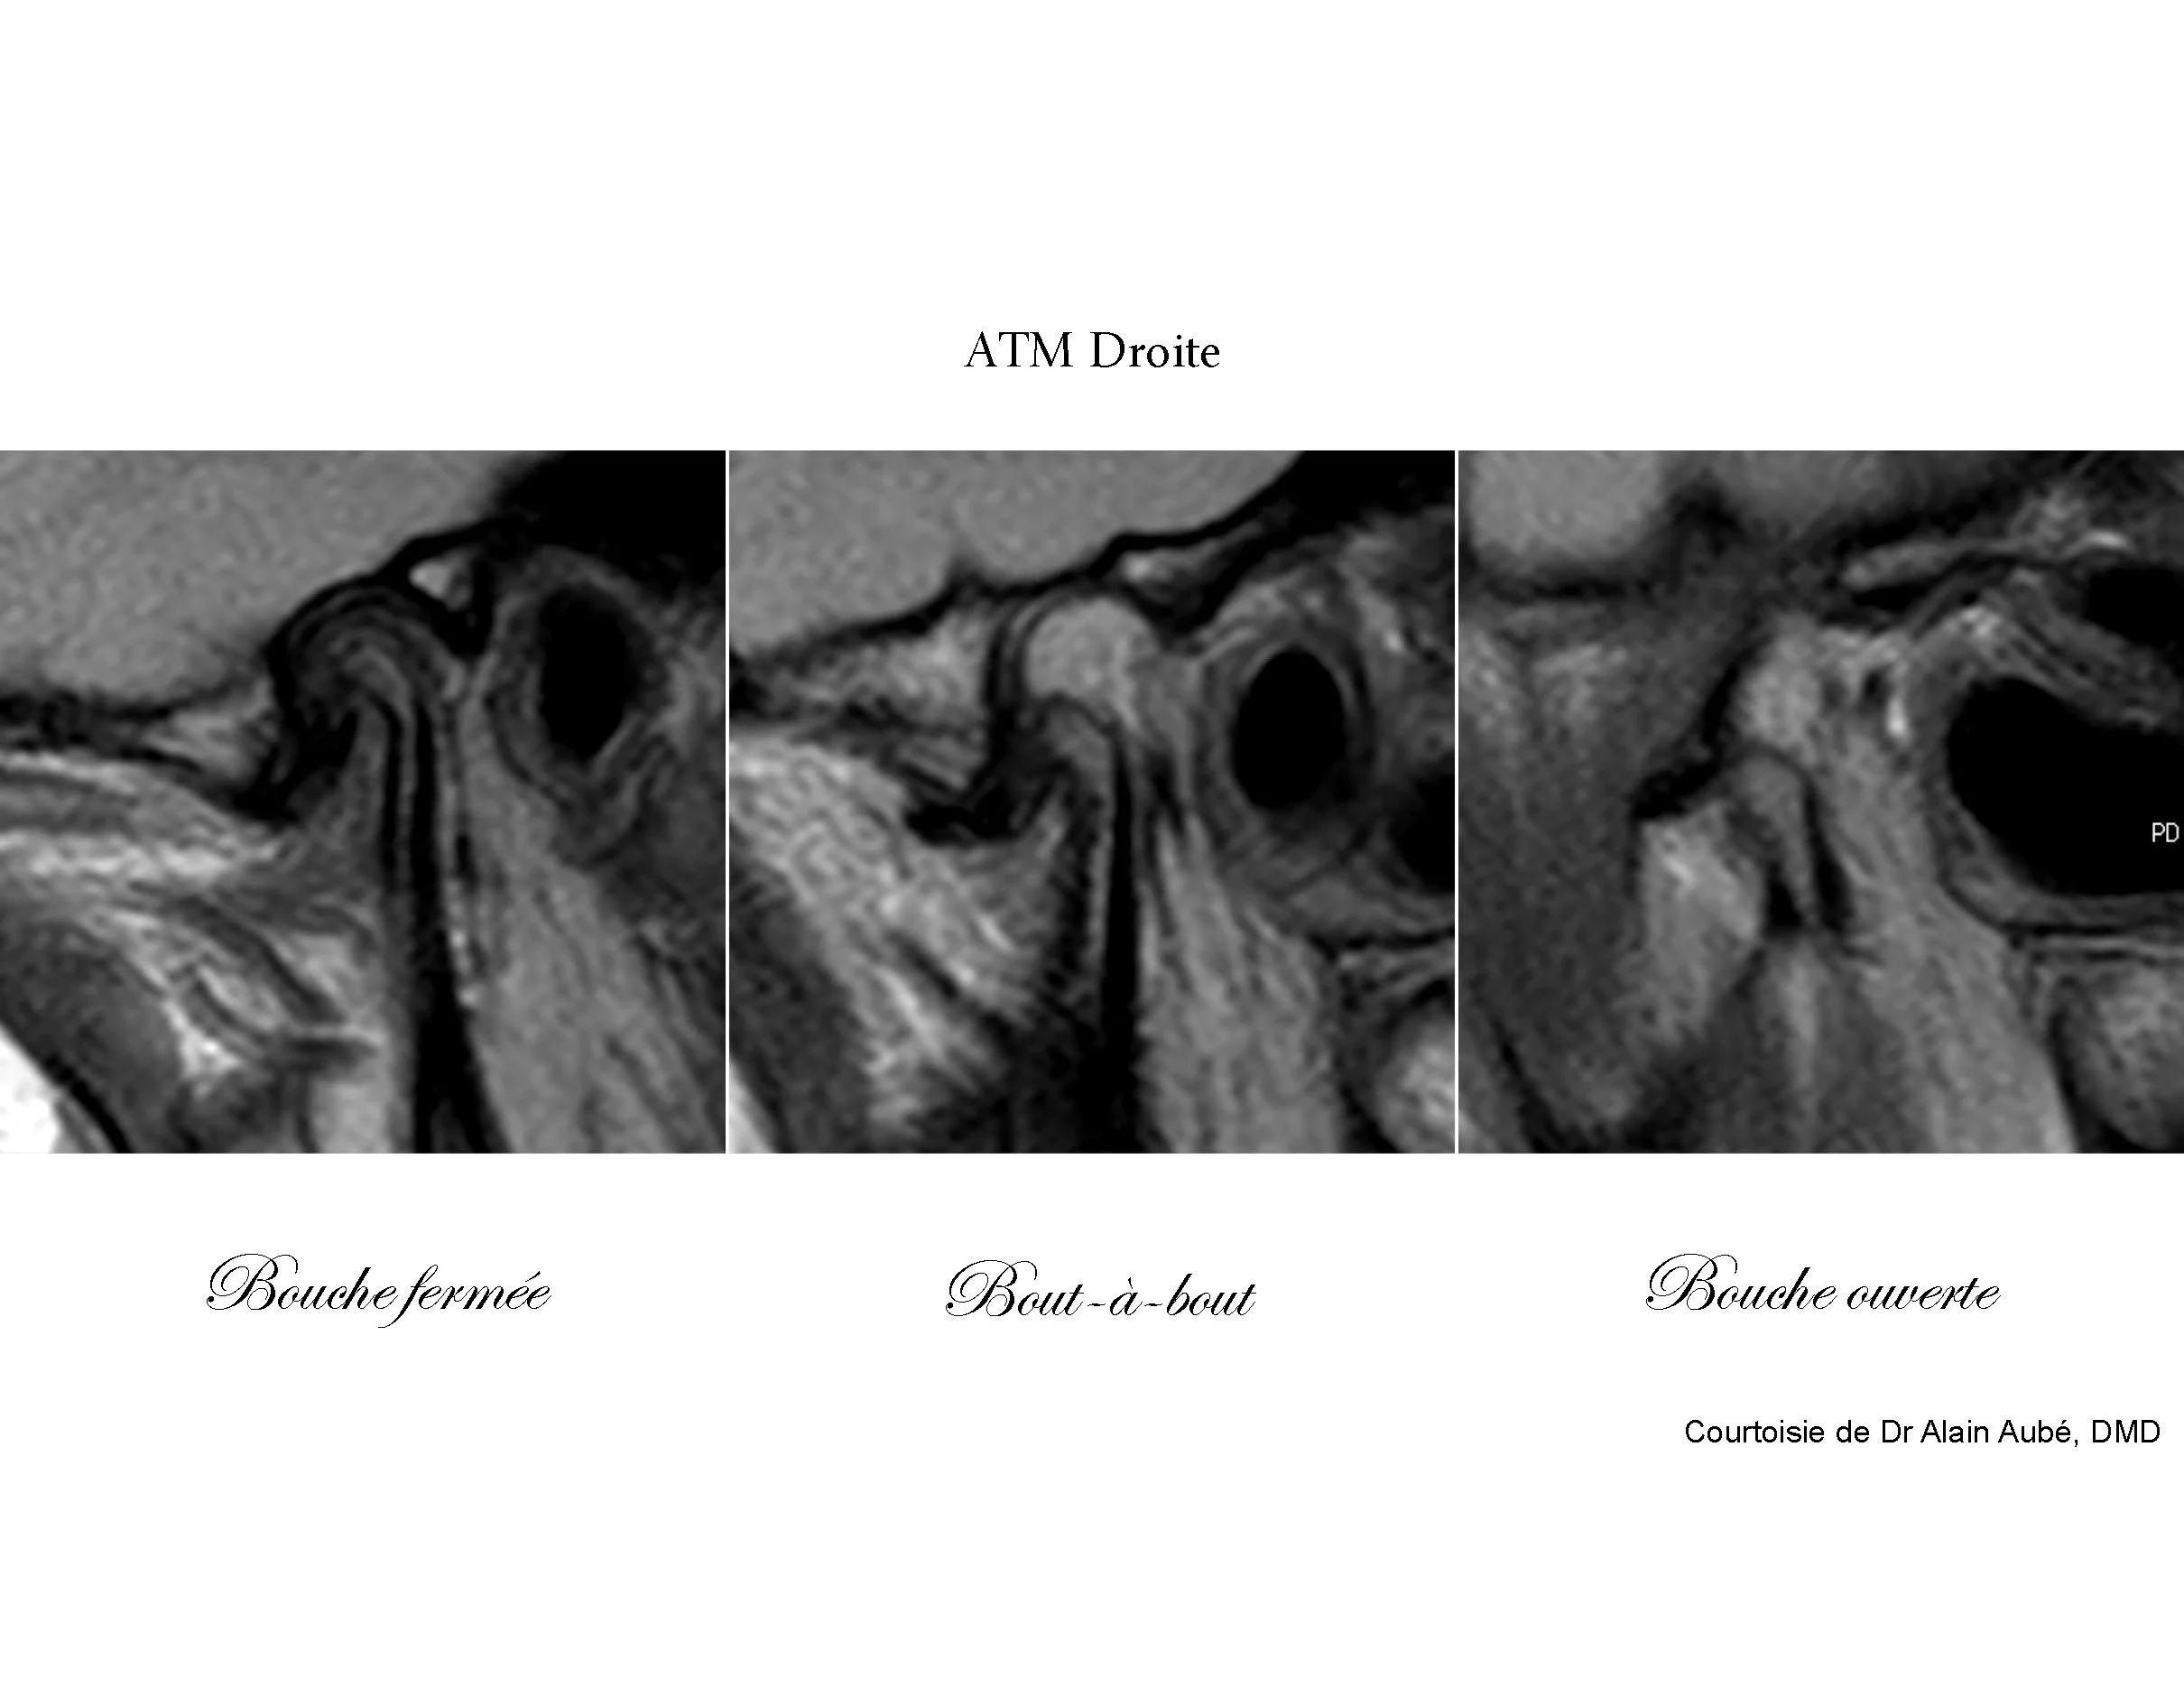

À l'IRM, les ATM présentent des déplacements discaux des deux côtés et apparaissent comme étant potentiellement instables.

Du côté droit le déplacement discal antérieur est sans réduction en bout-à-bout et en bouche ouverte. Le condyle présente une sous-croissance possiblement associée à une arthrose dégénérative avec une corticale instable. De l’inflammation peut être observée au fond de la fosse ainsi qu’au niveau du ptérygoïdien externe. La pathologie articulaire se situe au stade Piper 4B.

Du côté gauche, on observe également un déplacement discal antérieur mais cette fois-ci avec réduction en bout-à-bout et en bouche ouverte. Ce condyle présente aussi une sous-croissance possiblement associée à une arthrose dégénérative avec une corticale instable. De ce côté, l’inflammation est localisée au niveau du ptérygoïdien externe seulement. La pathologie articulaire se situe au stade Piper 4A.